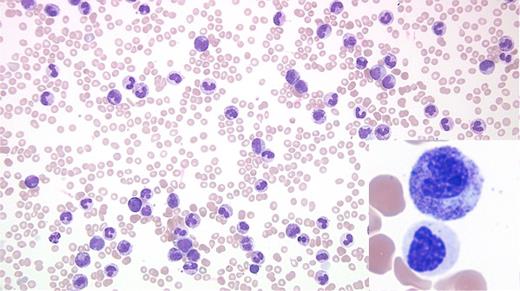

A 76-year-old man with a history of bladder cancer treated with two local resections and no chemotherapy or radiation was transferred from an outside hospital with hyperleukocytosis and an abnormal complete blood count (white blood cell count, 162 cells/μ; hemoglobin 8.2 g/dL; and platelet 43 K/uL) in 2017. His medical history was significant for mild leukocytosis and skin infections in 2006. Evaluation of peripheral blood revealed leukocytosis due to neutrophilia with two distinct subsets of neutrophils (Figure). Examination of marrow also showed abnormal findings.

The peripheral blood smear shows leukocytosis due to neutrophilia and some left shifted myeloid cells with two distinct morphologic subsets of neutrophils. The majority of the Figure shows toxic granulation, toxic vacuolation, and Döhle bodies, while the inset exhibits distinct dysplastic changes (nuclear hyposegmentation, abnormally condensed chromatin, and hypogranular cytoplasm). No peripheral blood basophilia, eosinophilia, or increased blasts are noted. Bone marrow evaluation revealed 100 percent cellular core with marked granulocytic proliferation with a left-shifted maturation and a population of dysplastic granulocytes along with markedly reduced erythropoiesis, and small and hypolobated megakaryocytes without any increase in blasts.

Karyotype analysis reveals a clonal t(7;17) (q22;q11.2) abnormality in 45 percent of the examined cells. Florescence in situ hybridization for BCR/ABL1 translocation, PDGFRB translocation, and 4q12 (PDGFRA-KIT) rearrangement was negative. CEBPA mutation detection by next-generation sequencing (NGS) was negative. Reverse-transcription polymerase chain reaction t(9;22) was negative for p210 and p190 transcripts. Large panel next-generation sequencing (NGS) reveals four distinct pathogenic mutations: two involving CSF3R (p.S810Qfs*6), and CSF3R (T618I), with additional mutations in SF3B1 and RAD21. The first mutation in the CSF3R gene leads to a premature C-terminal truncation resulting in dysregulation of SRC family-TNK2 kinase signaling. The second CSF3R produces a threonine to isoleucine substitution at amino acid 618. This results in dysregulation of JAK family kinase signaling. CSF3R mutations are seen in the majority of chronic neutrophilic leukemia (CNL) cases, but have been reported in less than 10 percent of atypical chronic myeloid leukemia (aCML).1,2

The above findings allowed classification as atypical CML, BCR-ABL1-negative. Because this entity is characterized by overlapping myeloproliferative features (leukocytosis and splenomegaly) and myelodysplastic features, it is currently classified under myelodysplastic/myeloproliferative neoplasm.3 Most such cases usually present with more striking granulocytic dysplasia. The patient was treated with off-label JAK2 inhibitor (ruxolitinib) and hydroxyurea with marked improvement in hemoglobin and platelet count as well as marked clinical improvement (resolution of splenomegaly and fatigue). The other important diagnostic considerations are CML and CNL. While there is peripheral blood neutrophilia with left shift and hypercellular marrow with small megakaryocytes, the presence of dysplasia and absence of BCR-ABL1 fusion allows exclusion of CML. Interestingly, the presence of CSF3R-T618I mutation and other CSF3R activating mutations have been included as part of the diagnostic criteria for CNL in 2016 WHO classification of myeloid neoplasms and acute leukemia.1 However, the diagnosis of CNL requires absence of dysplasia.

While leukemoid reaction resulting from a reactive process such as acute/chronic infection or an inflammatory disorder is certainly a possibility, the presence of clonal abnormalities (translocation and mutations) and morphologic dysplasia allows exclusion of a leukemoid reaction. The case highlights the need to carefully look for dysplasia even in cases that otherwise seemingly present with an infectious/leukemoid blood picture.